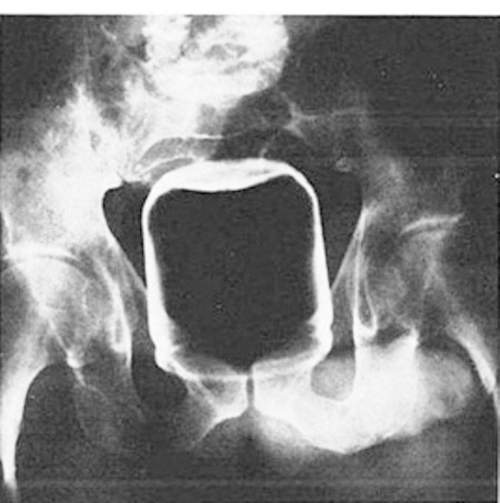

這是一個杯子~當它出現在異物突入X光照當中就變成了一個悲劇